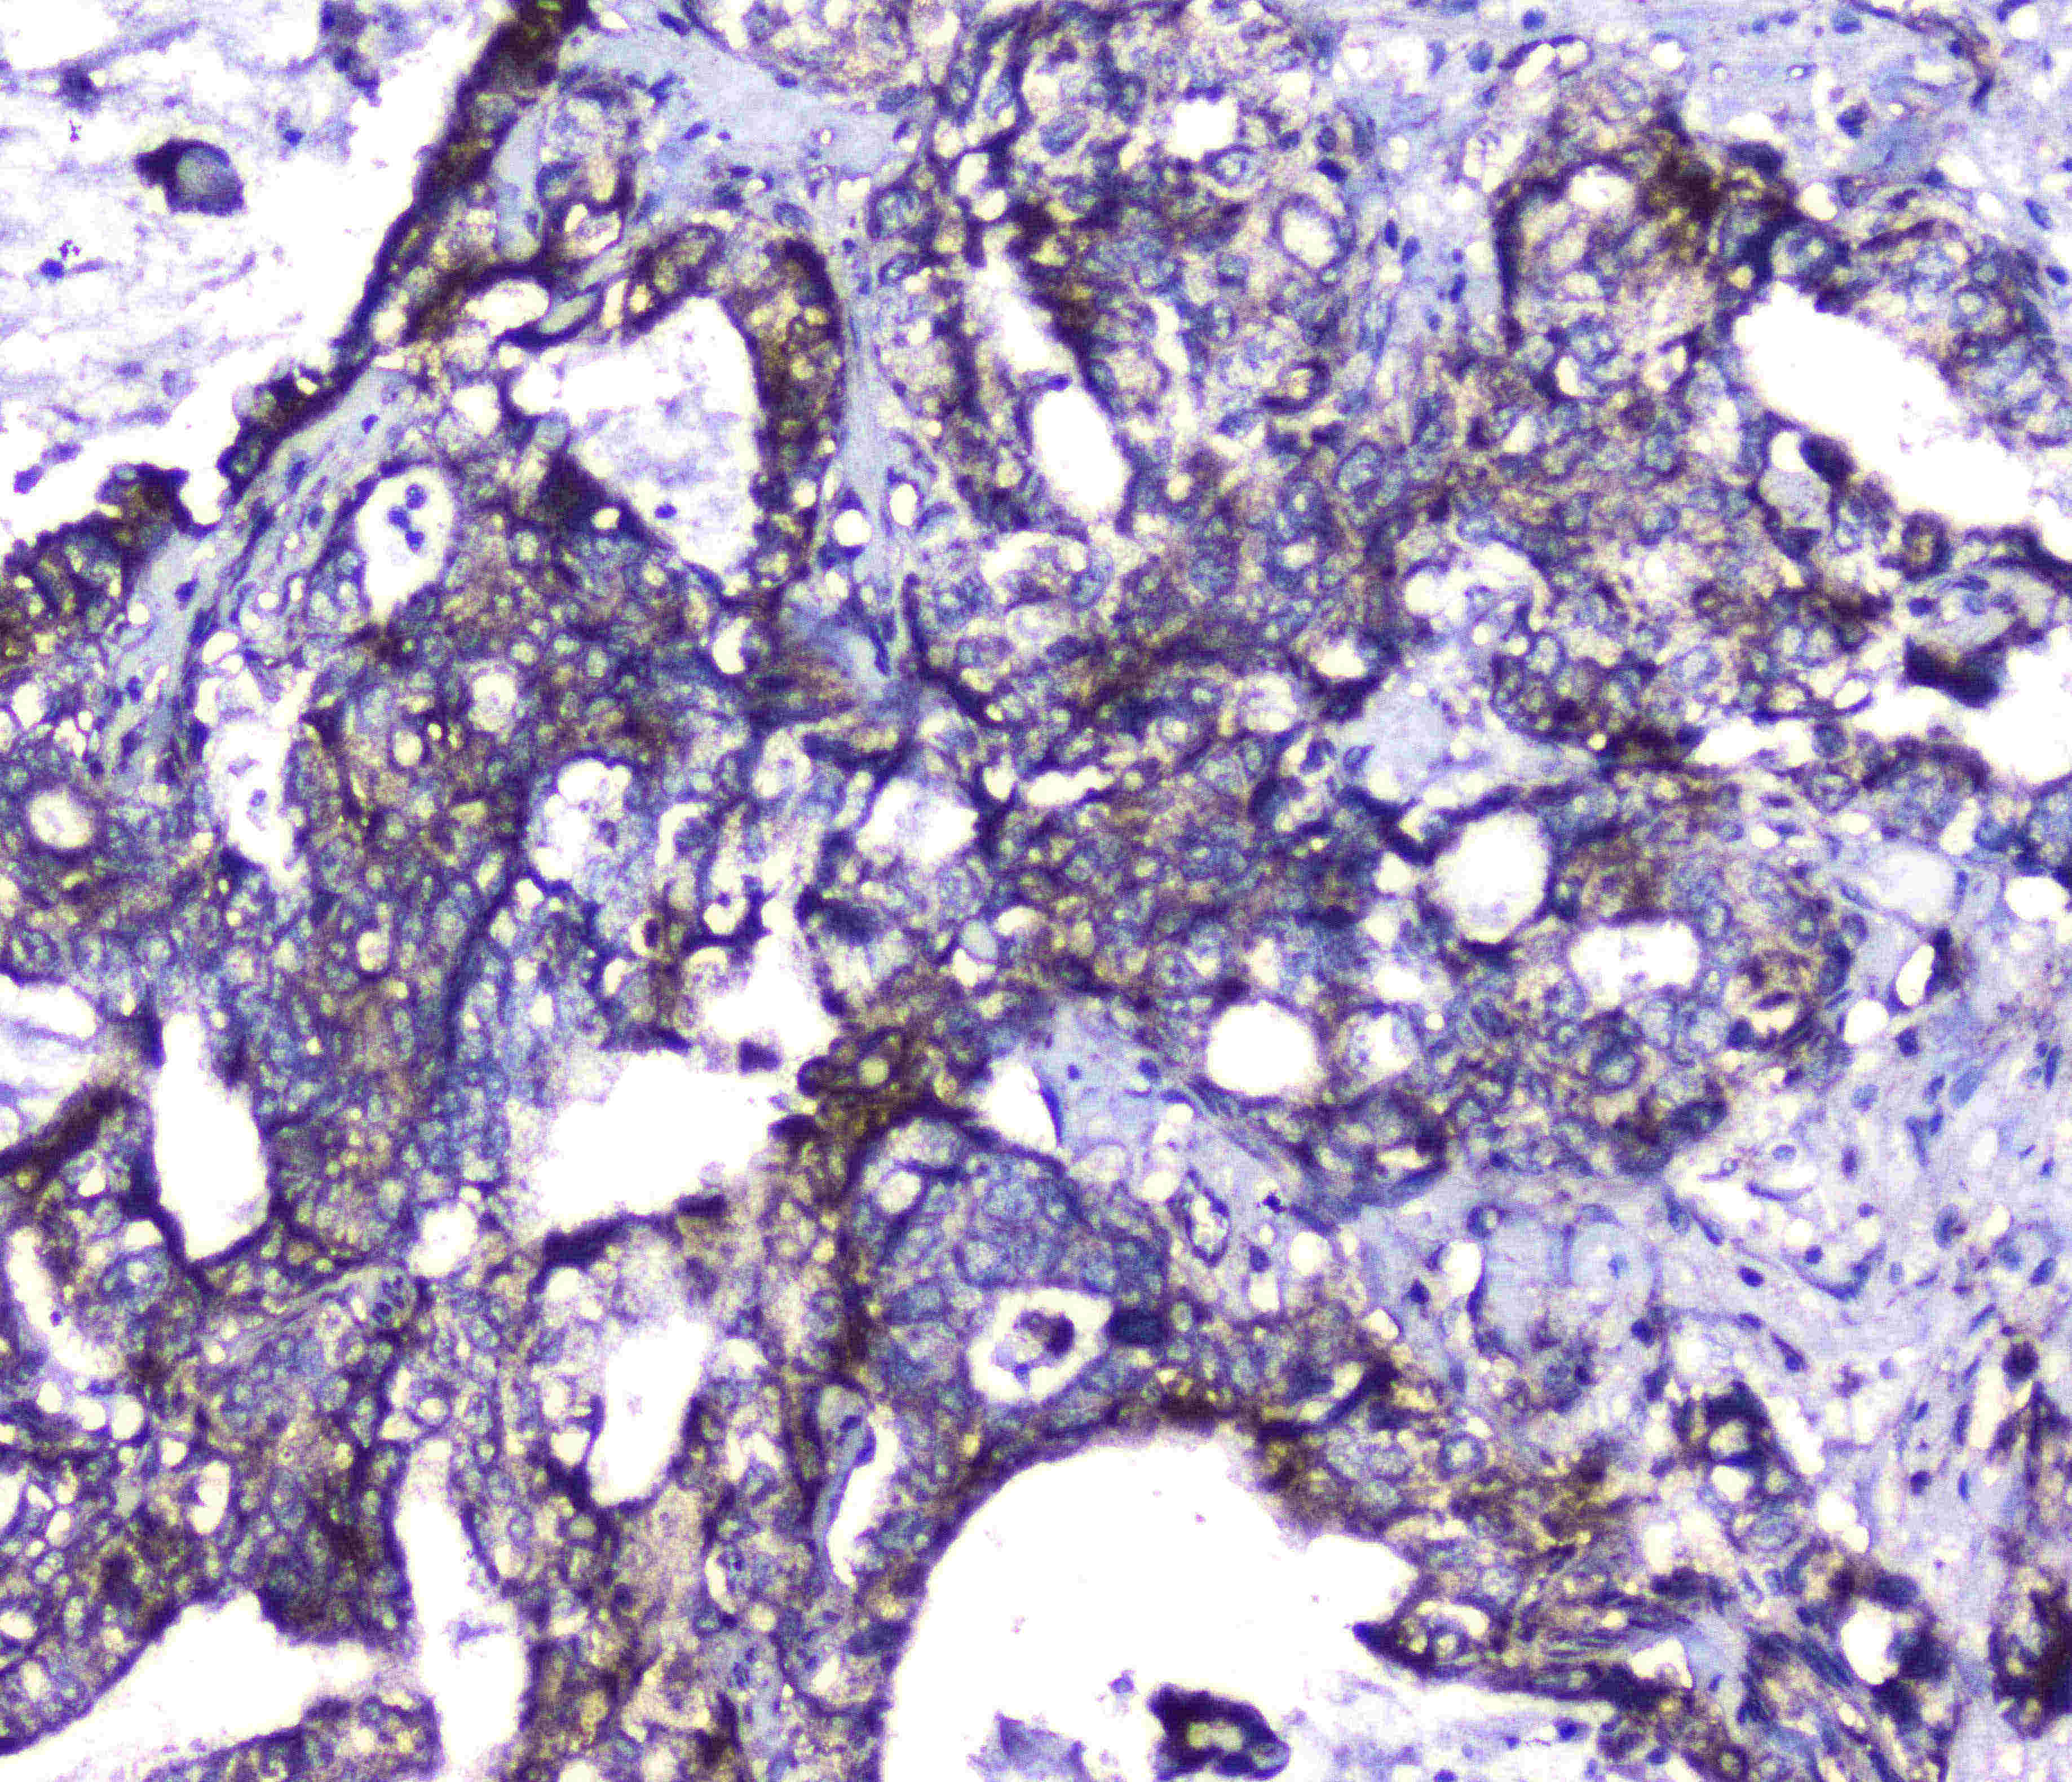

IHC analysis of CDK6 using anti-CDK6 antibody (PB1047).

CDK6 was detected in a paraffin-embedded section of human intestinal cancer tissue. Biotinylated goat anti-rabbit IgG was used as secondary antibody. The tissue section was incubated with rabbit anti-CDK6 Antibody (PB1047) at a dilution of 1:200 and developed using Strepavidin-Biotin-Complex (SABC) (Catalog # SA1022) with DAB (Catalog # AR1027) as the chromogen.